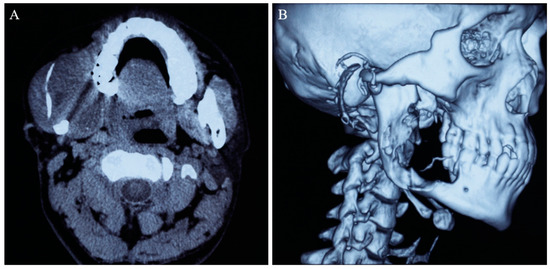

2. Case Report